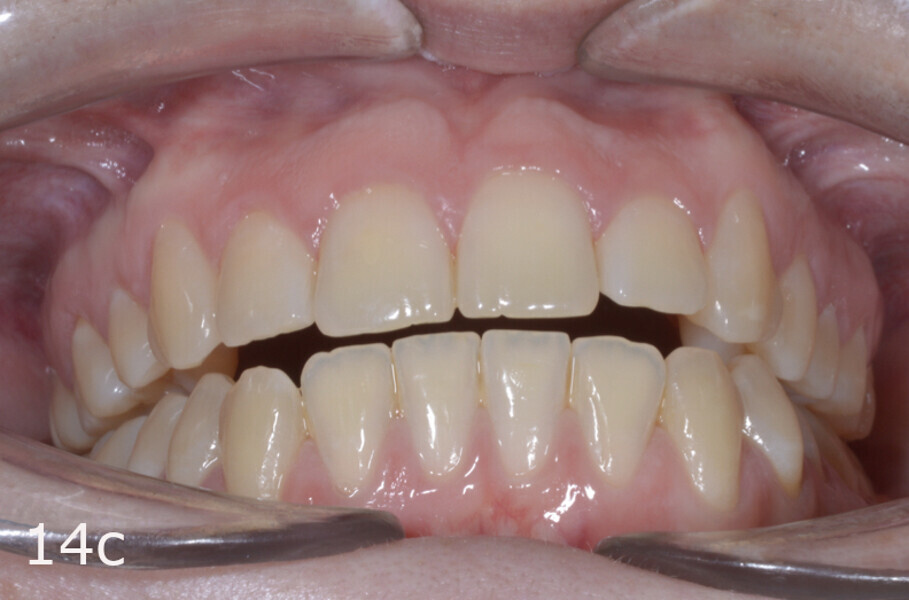

The total treatment time was 15 months. An Angle Class I relationship was established along with adequate anterior and canine guidance, establishing a functional occlusion. This not only ensures optimal masticatory function but also protects the teeth and the temporomandibular joint from excessive force. Maxillary and mandibular fixed retention were installed at the end of the treatment (Figs. 13–19).